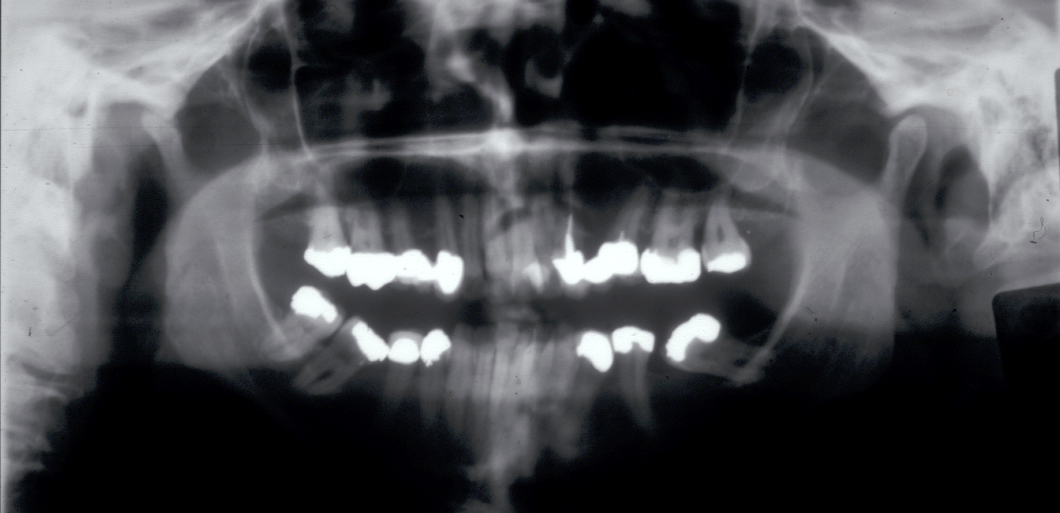

The temporomandibular joint is a complex three-dimensional structure and conventional radiographs only show a two-dimensional projection view, taken through one part of the joint. Only gross pathology can be picked up in this way (see Figure 5 for an example).

Figure 5: Panoramic X-ray radiograph showing a severely resorbed right condyle.